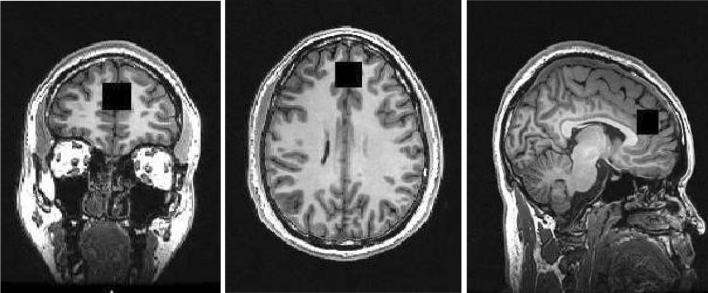

MRI scans were acquired using the General Electric MR750 3.0 T MRI scanner. High-resolution 3D T1-weighted structural MRI images were acquired for the 1H-MRS voxel prescription and anatomical co-localisation (in-plane matrix size of 256 × 256, FOV = 26.0 mm) using a whole-brain, sagittal IR-SPGR acquisition, and an eight-channel head coil (TR = 7.34 mm, TI = 400 ms, inversion time = 4 s, flip angle = 11°, and slice thickness = 1.2 mm). Data included here were previously published as a part of a multi-centre study [ref. 41]. The neuroimaging acquisition parameters for the acquisition of the proton magnetic resonance spectroscopy data were as follows: internal localizer scans were used to determine the anterior commissure–posterior commissure line and inter-hemispheric angle. For the voxel placement, the sagittal IR-SPGR scans were reformatted into axial and coronal planes and the voxel positioned in the ACC. This was followed by auto pre-scans for optimisation of water suppression and shimming of the MRS voxel. 1H-MRS spectra were acquired from the anterior cingulate region-of-interest (right-left 20 mm × anterior–posterior 20 mm × superior–inferior 20 mm). The placement of the anterior cingulate voxel was based on the midline sagittal localizer with the centre of the 20 mm × 20 mm × 20 mm voxel placed 13 mm above the anterior portion of the genu of the corpus callosum, perpendicular to the anterior commissure-posterior commissure line to minimize the inclusion of white matter and cerebral spinal fluid (CSF) (see Fig. 1 for images of the coronal, axial, and sagittal placement of the voxel). Finally, the 1H-MRS spectra (Point RESolves Spectroscopy (PRESS), TE = 30 ms, TR = 2 s) were obtained through the PROton Brain Examination (PROBE) sequence by GE, which includes water suppression. Water unsuppressed scans were also acquired for subsequent eddy current correction and water referenced metabolite quantification. A subset of these data (17 subjects) were reported previously [ref. 25]. As described previously [ref. 52], MRI scans were performed between 9:00 and 11:30 am; participants fasted (water was allowed) and abstained from alcohol and other substances for more than 12 h before undergoing the MRI scan.